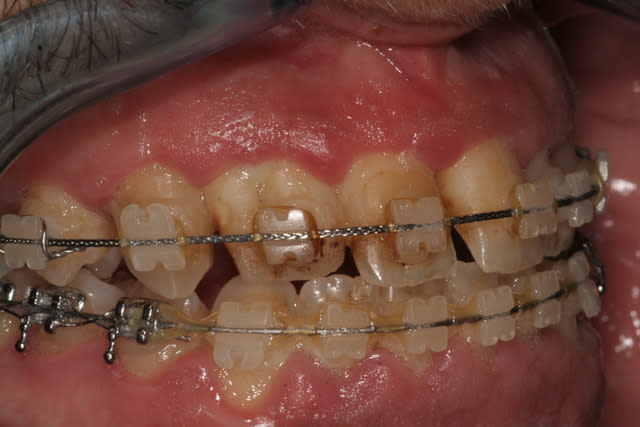

Si ça se trouve, vu la couleur des ligatures élasto et des chainettes il n'est pas allé chez son ortho depuis mille ans.

IL a du fil tressé rectangulaire au maxillaire et un fil rond à la mandibule, c'est pas ça qu'on met quand on termine un cas.

Il ne t'aurait pas demandé si c'était possible que ça soit toi qui lui dépose son multi attache par hasard?

Le patient n'est certainement pas sérieux vu la qualité du contrôle de plaque et l'état parodontal et c'est un motif suffisant pour mettre fin au ttt ODF.

Reste qu'il est étonnant que l'asymétrie 12/22 n'ait pas été gérée en amont par l'ODF, car même avec des facettes jamais le résultat ne pourra être satisfait. Si des facettes (ou compos) sont prévus pour gérer l'assymétrie 12/22 l'ortho doit en amont positionner les racines de manière idéale en contrôlant l'emplacement et la taille des diastèmes.